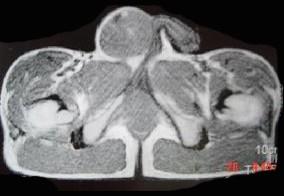

问题 29岁男性患者,右侧睾丸肿痛5个多月,行MRI检查,如图所示,T1加权见右侧阴囊内见球形肿块,呈中等信号,其内信号不均,T2加权肿块为高信号,最可能的结果是 ( )

选项 A、皮样囊肿 B、畸胎癌 C、睾丸结核 D、畸胎瘤 E、精原细胞瘤

答案 E